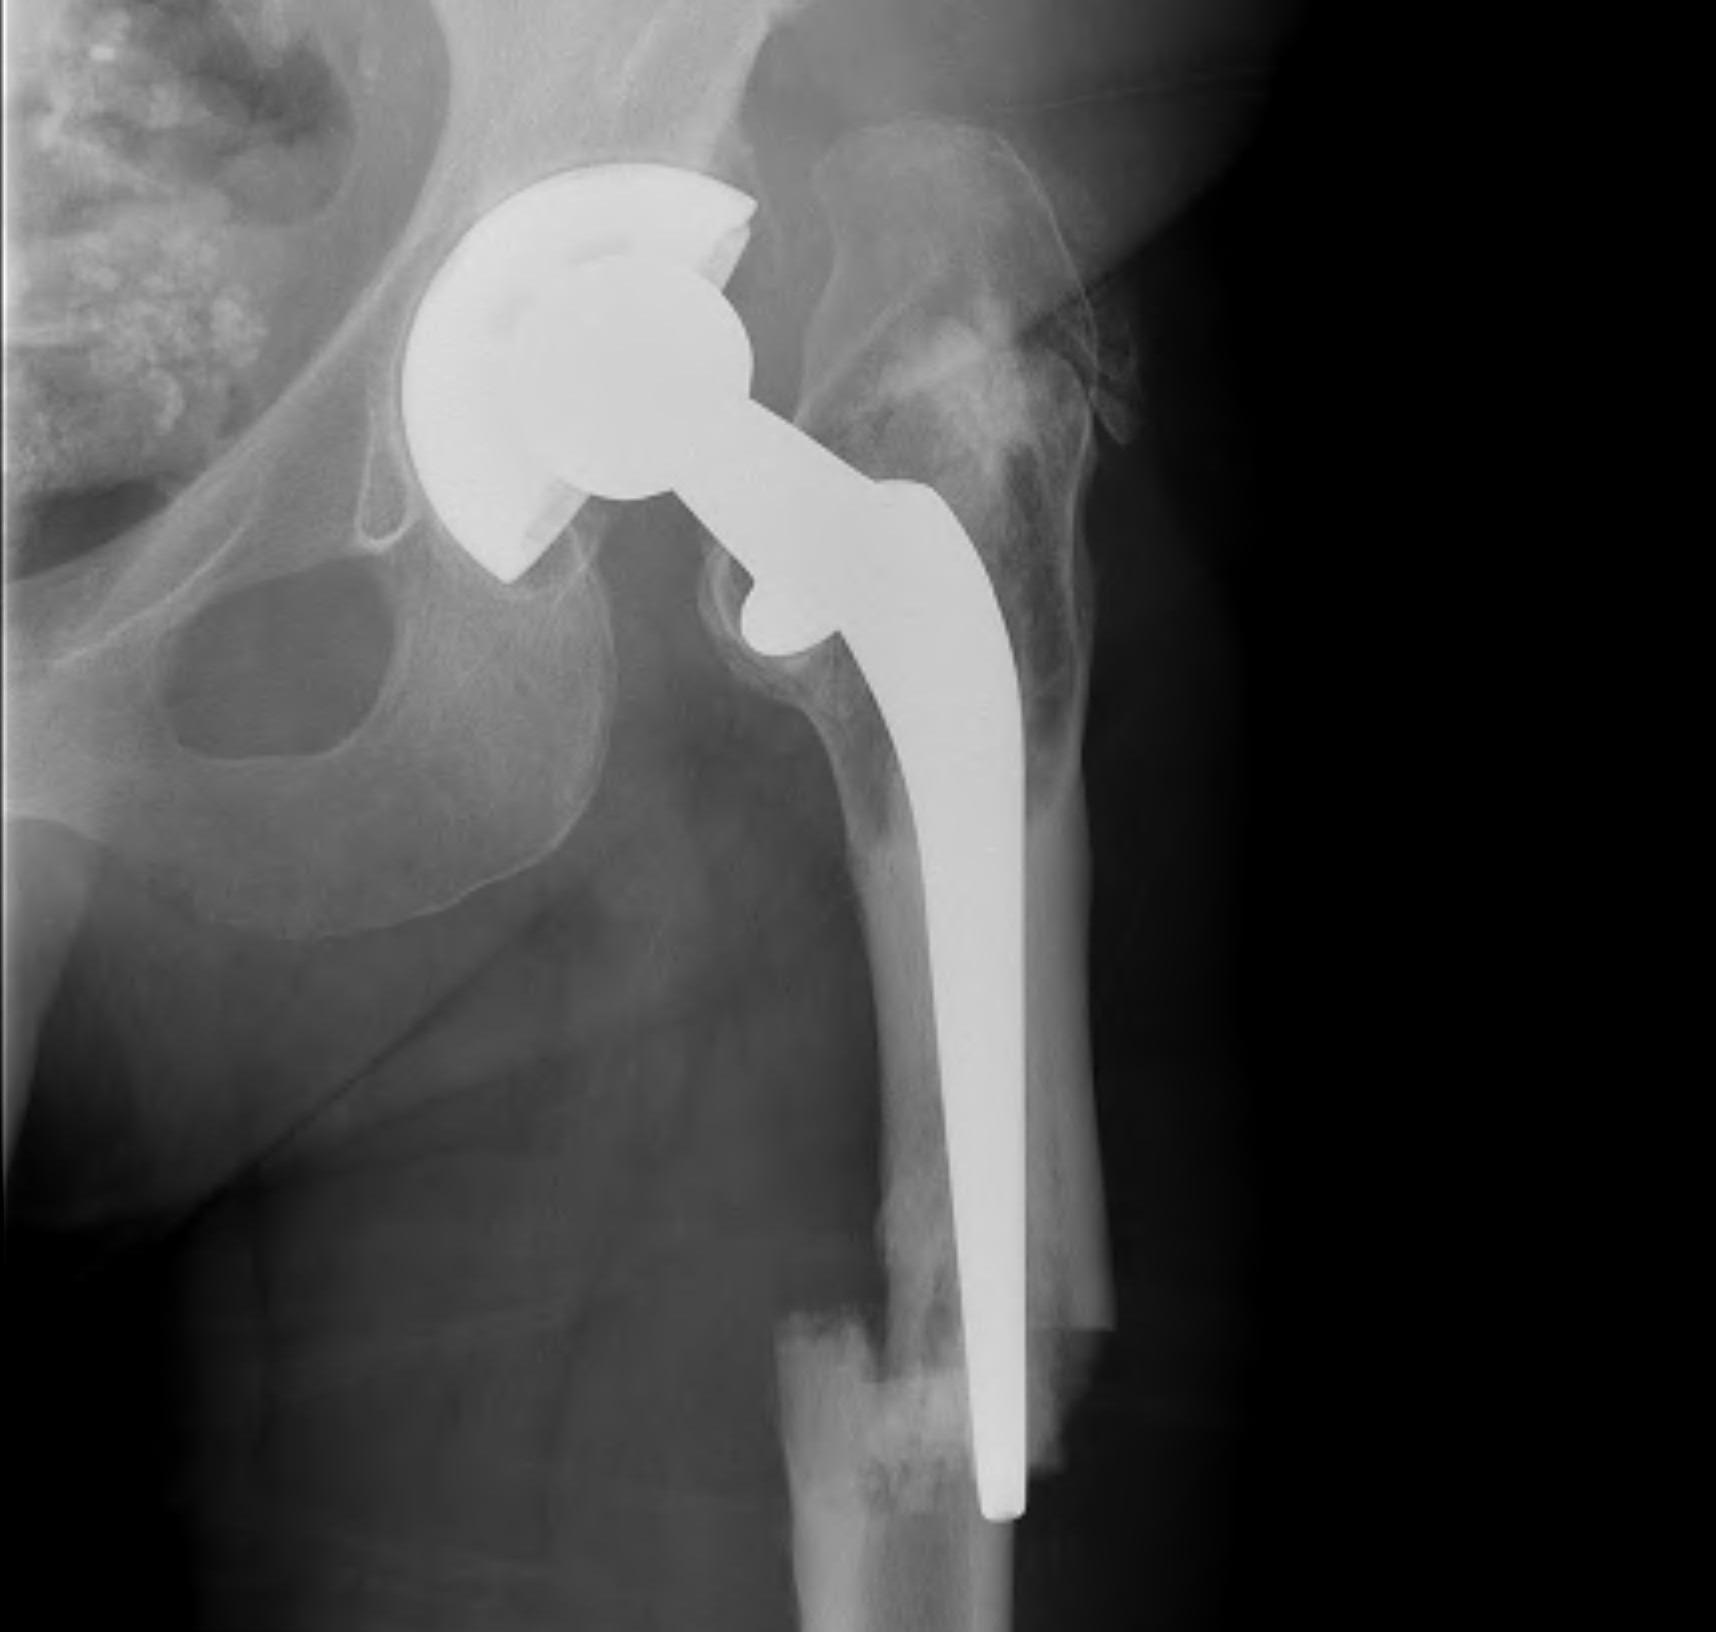

Fracture with stem subsidence around a polished tapered femoral stem treated with ORIF